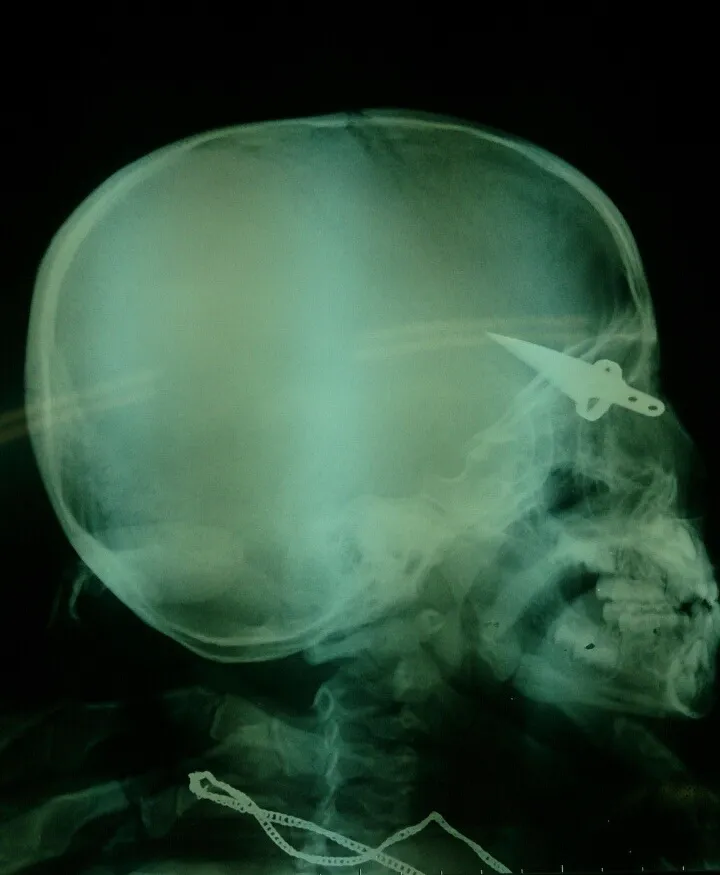

Phim chụp con dao cắm sâu vào thái dương bên phải bệnh nhi. Ảnh: BS Đặng Đỗ Thanh Cần.

Bệnh nhi đến BV Nhi Đồng 2 trong tình trạng lưỡi dao cắm lút vào đầu, sâu khoảng 3 cm, trong đó xuyên qua sọ vào não gây dập não và chảy máu dưới màng cứng. Các BS đã tiến hành mổ cấp cứu lấy máu tụ, cắt lọc mô não dập và rút dao ra từ từ, đốt cầm máu và chống nhiễm trùng.

"Điểm đặc biệt là mũi dao nằm cách mạch máu lớn trong não một cm. Nếu lưỡi dao cắt đúng mạch máu thì khả năng cháu bé sẽ chết trên đường đi chuyển viện”, BS Cần nói.